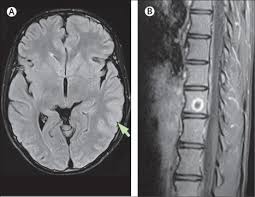

Two subtypes are recognised which differ in demographics, virus, and pattern of involvement. Mri demonstrates extensive edema in the right temporal lobe with areas of intrinsic high t1 signal, in keeping with hemorrhage. Terminology the entity or closely related variants have also been. Coccidioidal meningitis refers to central nervous system involvement of the dimorphic fungus coccidioides spp, mainly coccidioides immitis and coccidioides posadasi. Note the high signal in the caudate heads and putamen on flair.

Pcr was repeated on the biopsy specimen and was positive for hsv. Limbic encephalitis, mca ischaemia, tumours, effects of seizures) hyperintense t2 signal in the medial temporal lobes, inferior frontal lobes and insula basal ganglia are usually spared Axial t2 prominent swelling, increase t2 signal involving the left temporal lobe and insular cortex. Multilocularis, and describes a spectrum of disease involving the spinal cord, the spine, or both. Mri is the diagnostic modality of choice abnormal in 90%; A brain biopsy was performed and the histology was consistent with encephalitis. Mri demonstrates extensive edema in the right temporal lobe with areas of intrinsic high t1 signal, in keeping with hemorrhage. For a general discussion, and for links to other system specific manifestations, please refer to the article on hydatid disease.

The basal ganglia are usually spared. Mri is the diagnostic modality of choice abnormal in 90%; Hsv encephalitis | radiology case | radiopaedia.org. Axial t2 prominent swelling, increase t2 signal involving the left temporal lobe and insular cortex. For a general discussion, and for links to other system specific manifestations, please refer to the article on hydatid disease. Herpes simplex (hsv) encephalitis is the most common cause of fatal sporadic fulminant necrotizing viral encephalitis and has characteristic imaging findings. Herpes simplex virus (hsv) is a human herpesvirus that causes hsv encephalitis (hse), which is the commonest fatal sporadic encephalitis in humans. Hse may result from primary infection or reactivation from latency, and it frequently involves frontal or temporal lobes, as well as the brain stem. The differential diagnoses include limbic encephalitis (paraneoplastic), gliomatosis cerebri, and status epilepticus. A brain biopsy was performed and the histology was consistent with encephalitis. For a general discussion, and for links to other system specific manifestations, please refer to the article on hydatid disease. Cerebral malaria is a rare intracranial complication of a malarial infection. Bilateral temporal lobe t2 hyperintensity refers to hyperintense signal involving the temporal lobes on t2 weighted and flair imaging.

Two subtypes are recognised which differ in demographics, virus, and pattern of involvement. Terminology cerebritis is essentially the same as encephalitis except that it is used to denote brain par. There is also some cortical ribboning seen on dwi. Hsv encephalitis | radiology case | radiopaedia.org. Herpes simplex encephalitis (hse) is the most common form of viral sporadic encephalitis and, when left untreated, has a mortality rate of 70% (3, 22).

The changes spare the basal ganglia, a feature which is helpful in distinguishing an mca infarct with hemorrhagic transformation from herpes simplex encephalitis, the diagnosis in this case. Hse may result from primary infection or reactivation from latency, and it frequently involves frontal or temporal lobes, as well as the brain stem. Herpes simplex (hsv) encephalitis is the most common cause of fatal sporadic fulminant necrotizing viral encephalitis and has characteristic imaging findings. It is usually bilateral but asymmetrical. The differential diagnoses include limbic encephalitis (paraneoplastic), gliomatosis cerebri, and status epilepticus. Two subtypes are recognized which differ in demographics, virus, and pattern of involvement. Given the history of fever and seizures coupled with the mri findings of bilateral mesial temporal lobe changes, herpes encephalitis requires clinical consideration. Spinal hydatid disease is an uncommon manifestation of hydatid disease, caused by the larval stage of echinococcus granulosus, or less commonly e. Multilocularis.the larval stage is the cause of hydatid disease in humans 1. The differential diagnoses include limbic encephalitis (paraneoplastic), gliomatosis cerebri, and status epilepticus. Herpes simplex encephalitis (hse) is the most common form of viral sporadic encephalitis and, when left untreated, has a mortality rate of 70% (3, 22). This patient went on to have hsv encephalitis proven on csf pcr. Bilateral temporal lobe t2 hyperintensity refers to hyperintense signal involving the temporal lobes on t2 weighted and flair imaging.